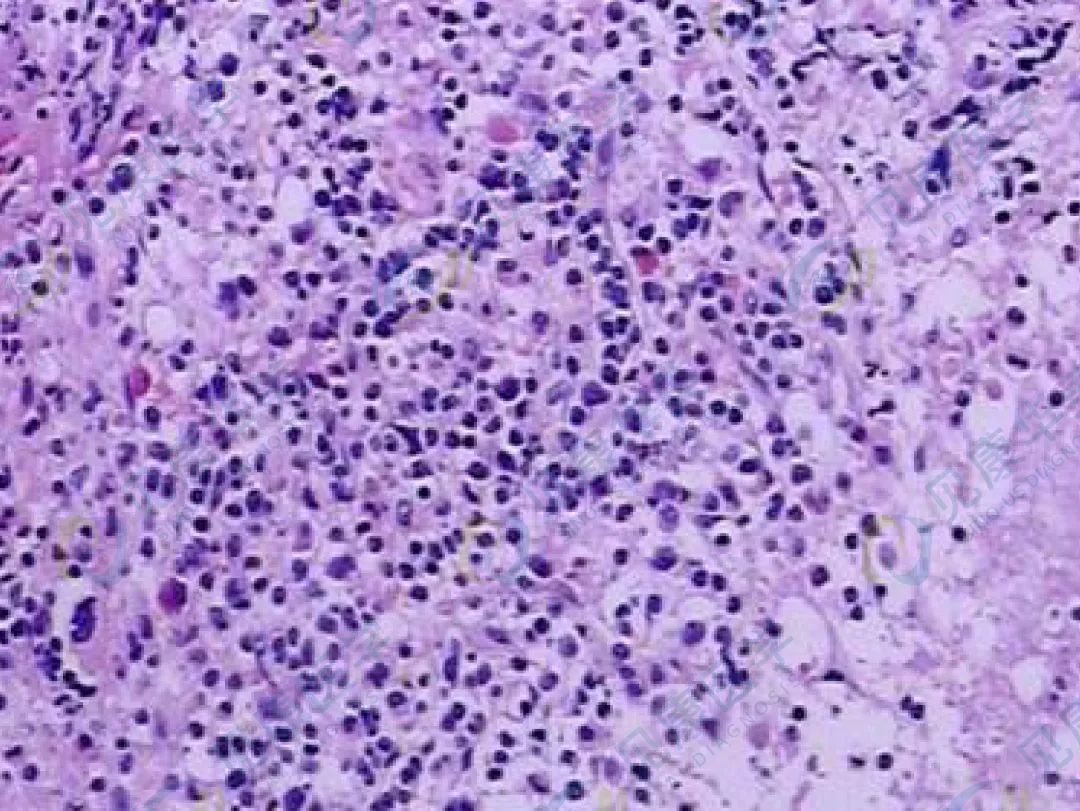

形态学

肿瘤细胞呈多样性,可表现为多形性小细胞、中等大细胞、大细胞和间变型多种形态特点。典型的形态为胞体中等至大的细胞,核扭曲或分叶,“花细胞”(核呈多叶状)具有特征性。骨髓侵犯不明显,侵犯程度与外周血肿瘤细胞的负荷之间不成比例(外周血肿瘤细胞募集自其他器官,如皮肤)。

ATLL外周血涂片中的“花细胞”